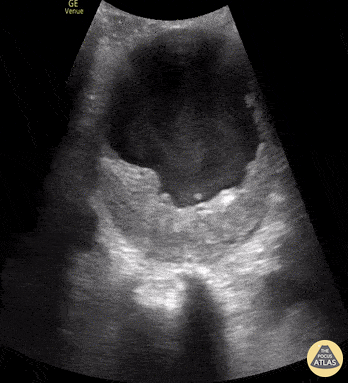

A 70-year-old male presented as a trauma alert and was found to have this 10 cm abdominal aortic aneurysm (AAA) with associated echocardiographic smoke! Echogenic smoke is produced by the intersection of RBC’s and plasma proteins at low shear rate conditions. Brian Toston, Internist. Adventura, FL